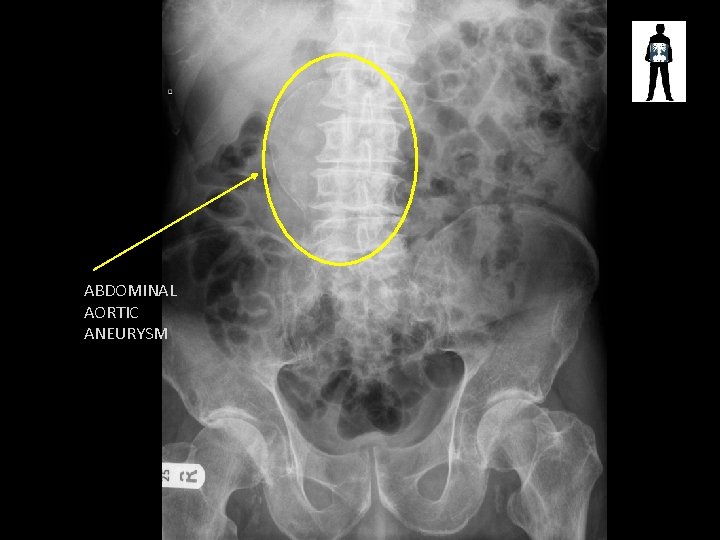

ABDOMINAL AORTIC ANEURYSM

Aortic Aneurysm • Stretching and swelling of the muscle layers in the aorta (usually around 2. cm diameter) • Causing loss of blood pressure, pulsating feeling • Large aneurysms (5 cm or greater) are at risk of rupture, dissection internal bleeding and death. • Some can be treated depending on their location